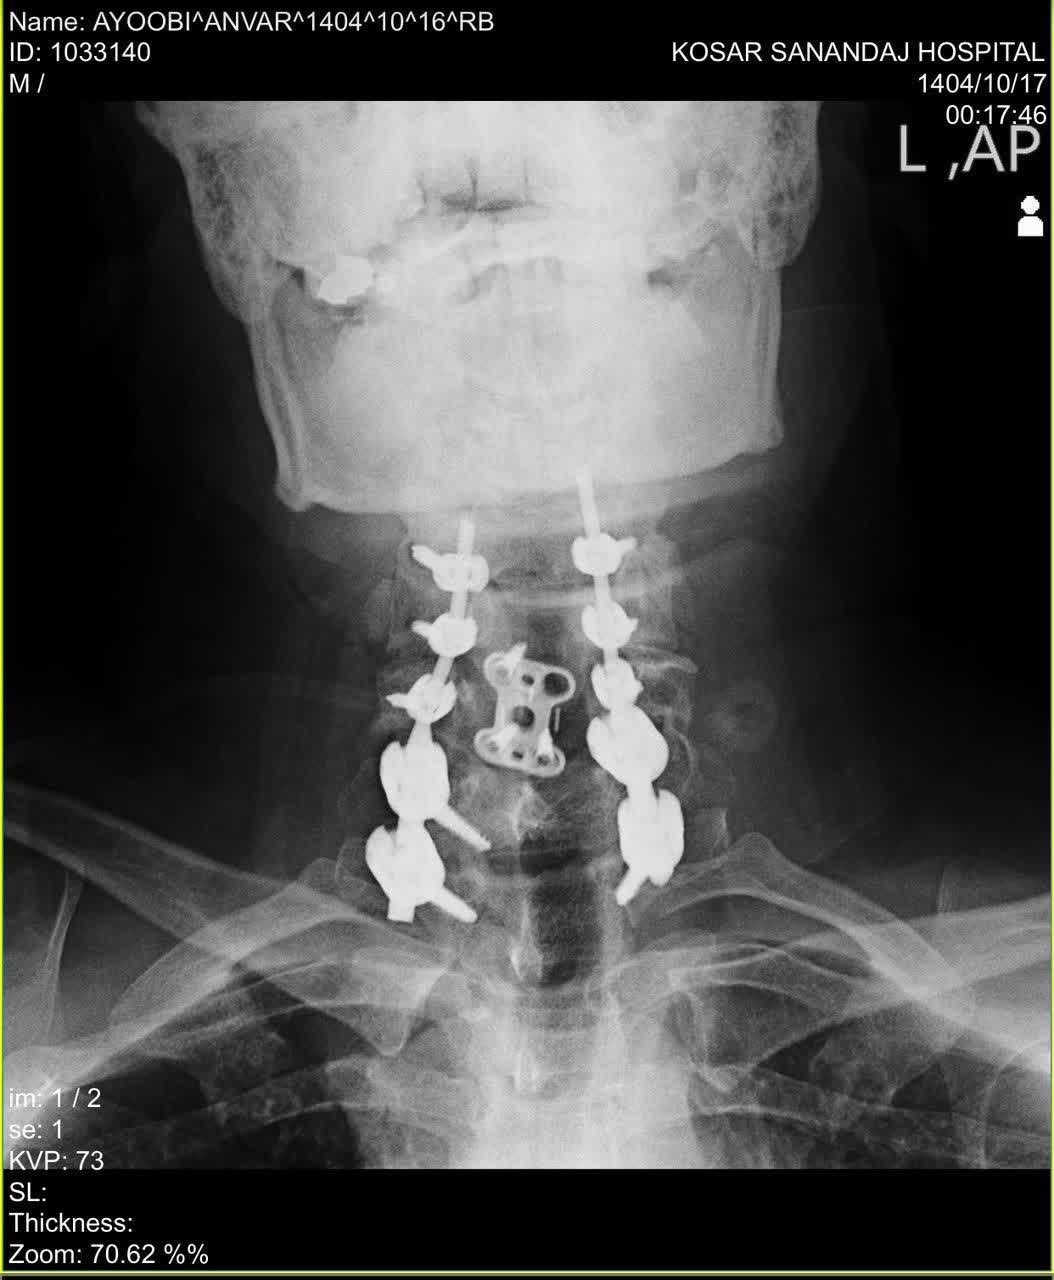

دکتر محمدی در توضیح مرحله اول جراحی گفت: در مرحله اول، از طریق برش در پشت گردن (رویکرد خلفی)، اقدام به آزادسازی وسیع نخاع (Decompressive Laminectomy از C5 تا C7) و سپس تثبیت ستون فقرات با استفاده از پیچ و میله (Posterior Cervicothoracic Fixation) کردیم. کل این فرآیند حساس تحت نظارت مداوم دستگاه نورومانیتورینگ Intraoperative انجام شد تا کوچکترین تماس یا فشاری بر نخاع یا ریشه‌های عصبی بلافاصله شناسایی و از بروز آسیب پیشگیری شود. خوشبختانه این مرحله با موفقیت پشت سر گذاشته شد.

وی در مورد مرحله دوم که چهار روز بعد انجام شد، توضیح داد: در این مرحله، از طریق برشی در جلوی گردن (رویکرد قدامی) به محل آسیب دسترسی پیدا کردیم. دیسک تخریب شده و بیرون زده که به کانال نخاعی فشار وارد می‌کرد را به طور کامل تخلیه کرده (Anterior Discectomy) و برای حفظ ثبات ناحیه، از یک کیج (Cage) مخصوص پر شده با مواد استخوانی استفاده نمودیم. در نهایت نیز با قراردادن یک پلیت (Plate) و پیچ در سطح مهره‌های مجاور، تثبیت نهایی را انجام دادیم. این مرحله نیز با موفقیت کامل به پایان رسید.